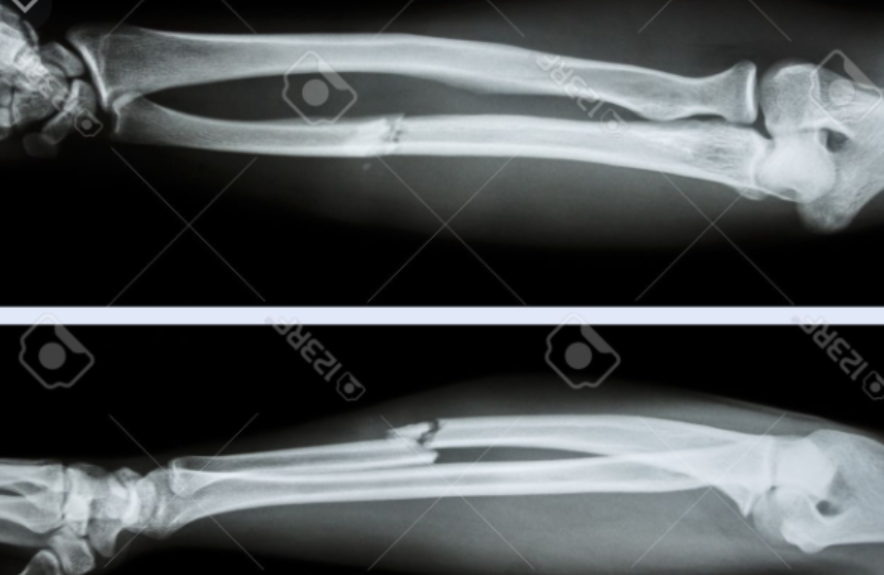

Fractura que se presenta en esta radiografia

Fractura de Smith

Mecanismo de accion de esta fractura

Caida sobre mano en flexion con antebrazo en supinacion

Deformida que presentan los pacientes con esta fractura

En pala de jardin